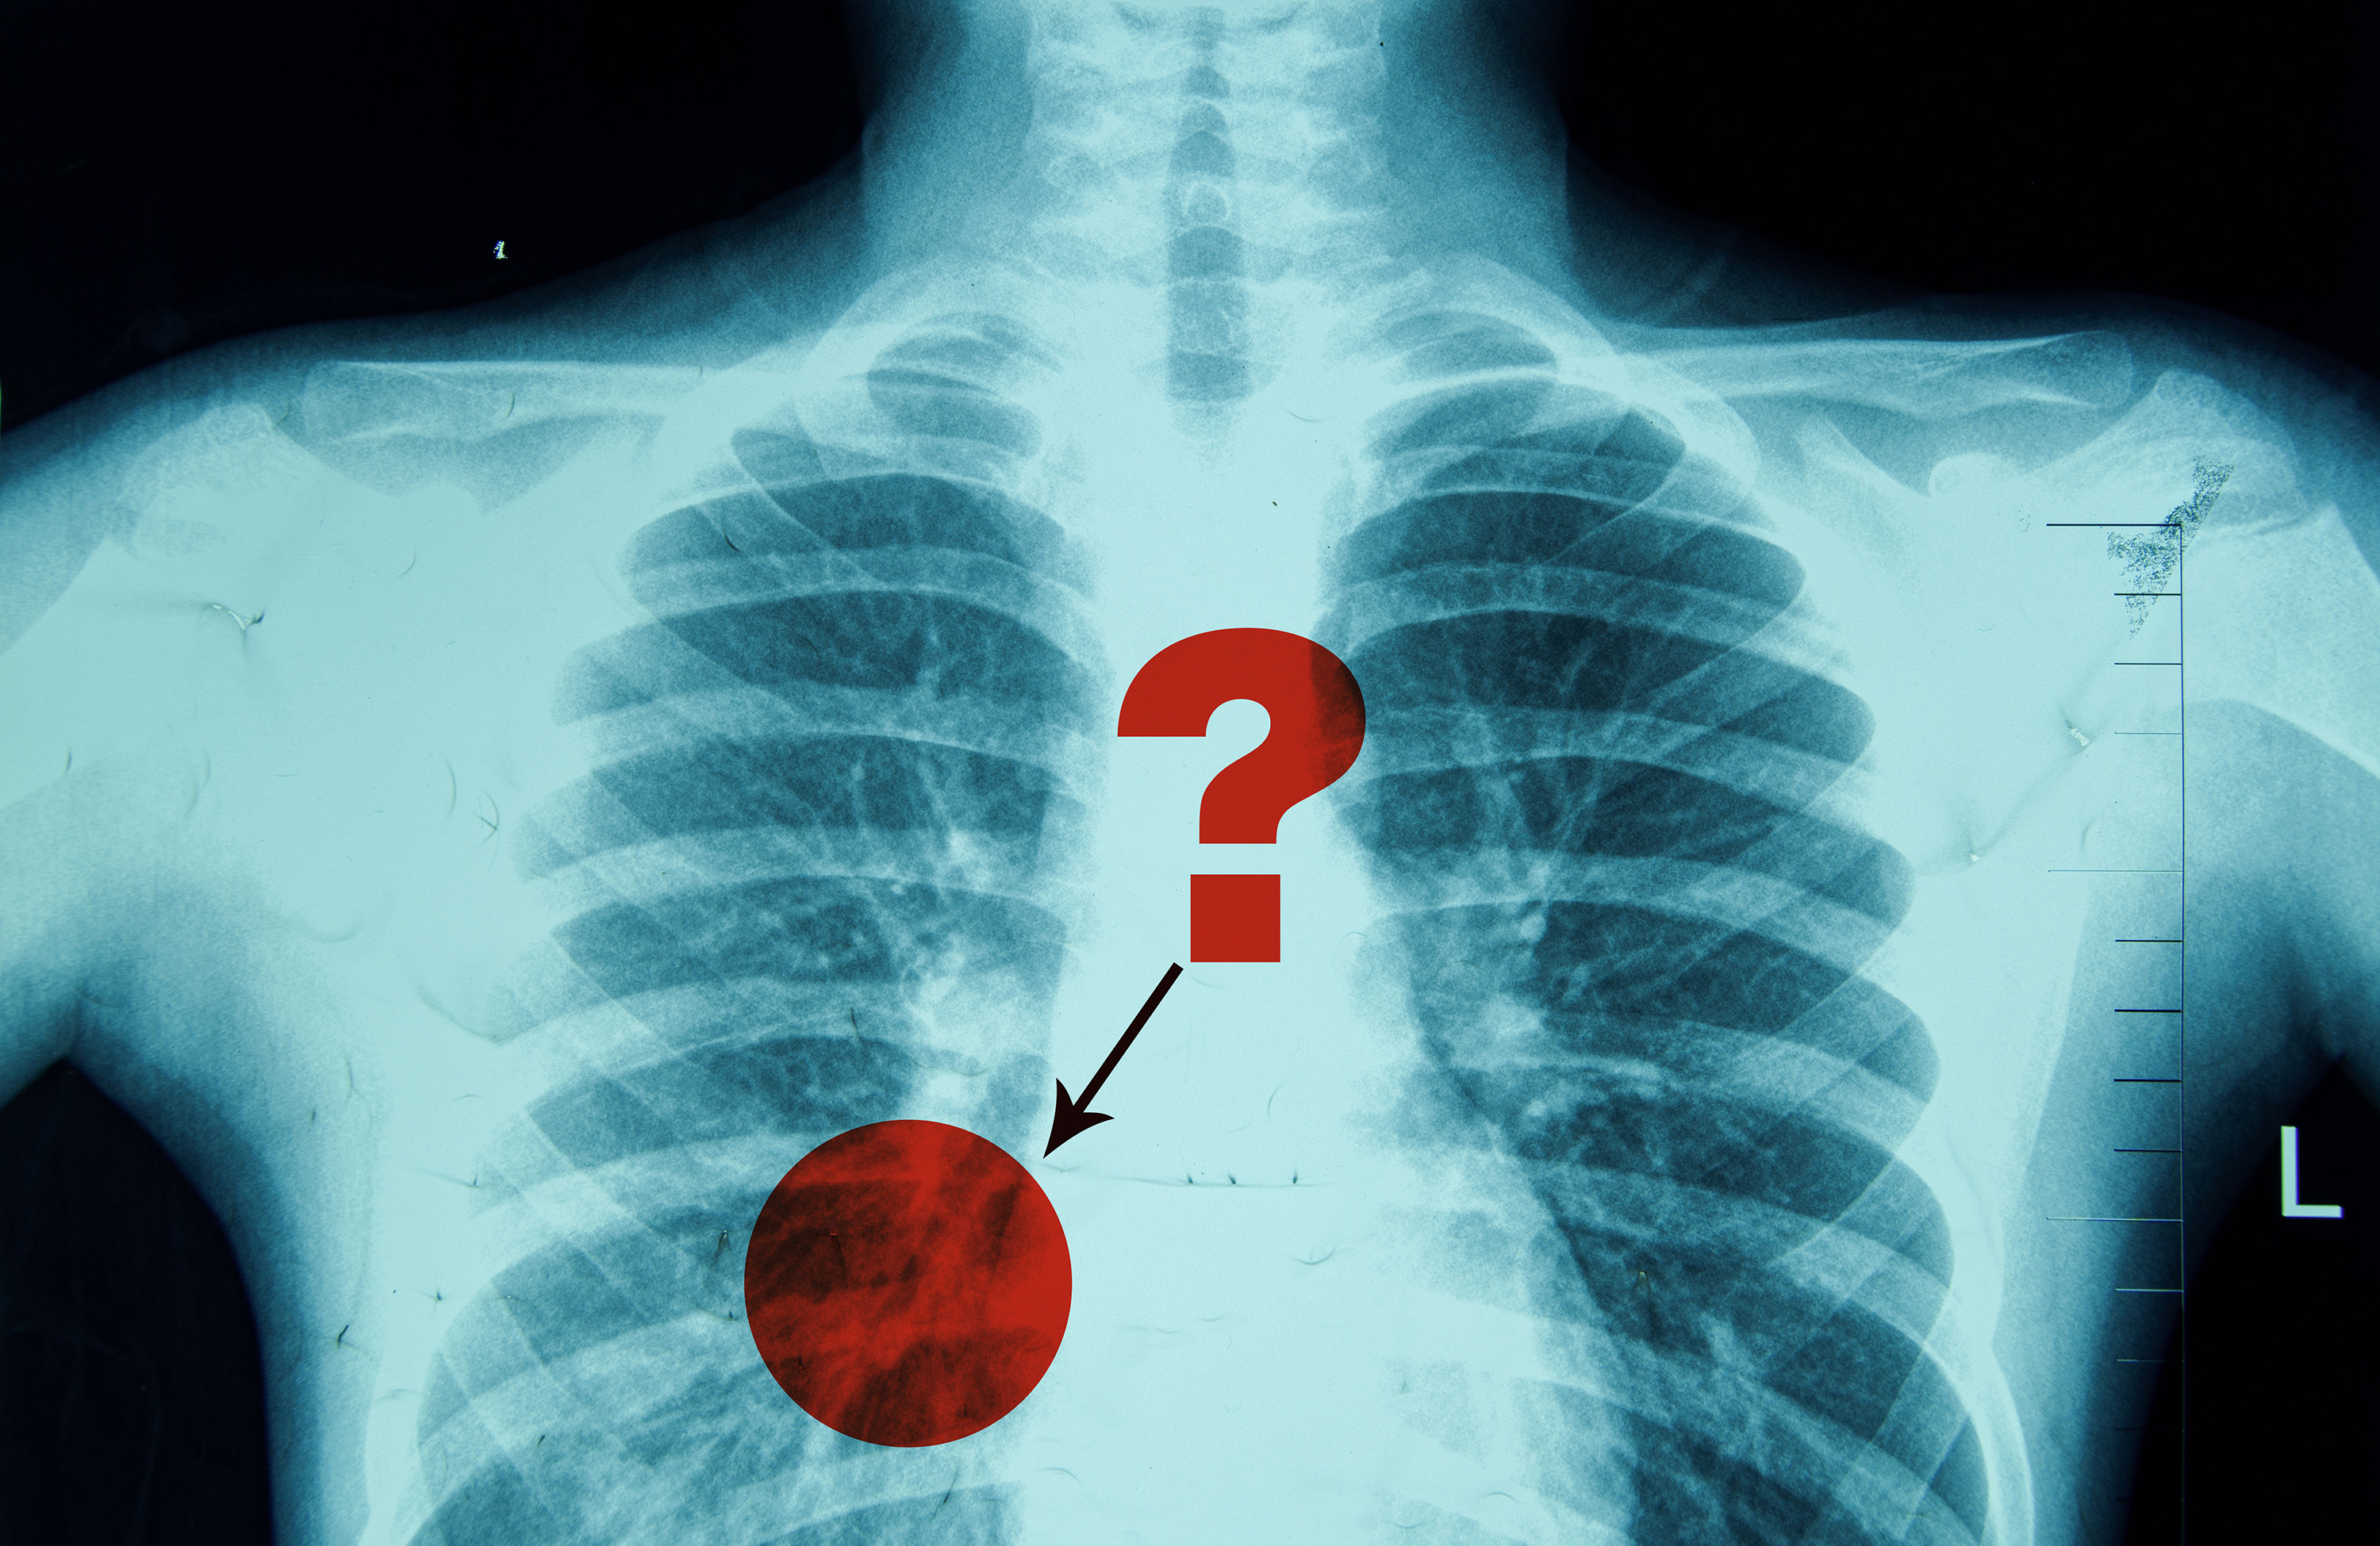

Because of the inherent ambiguity in medical photos like X-rays, radiologists usually use phrases like “might” or “possible” when describing the presence of a sure pathology, akin to pneumonia.

A radiologist writing a report a few chest X-ray may say the picture reveals a “attainable” pneumonia, which is an an infection that inflames the air sacs within the lungs. In that case, a health care provider might order a follow-up CT scan to verify the analysis.

Nonetheless, if the radiologist writes that the X-ray reveals a “possible” pneumonia, the physician may start therapy instantly, akin to by prescribing antibiotics, whereas nonetheless ordering further exams to evaluate severity.